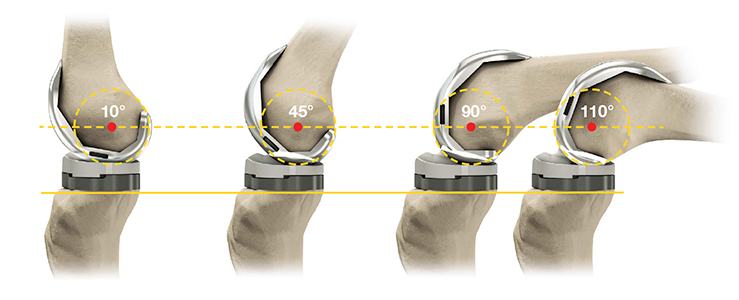

Фотографии и примеры протезирования коленного сустава